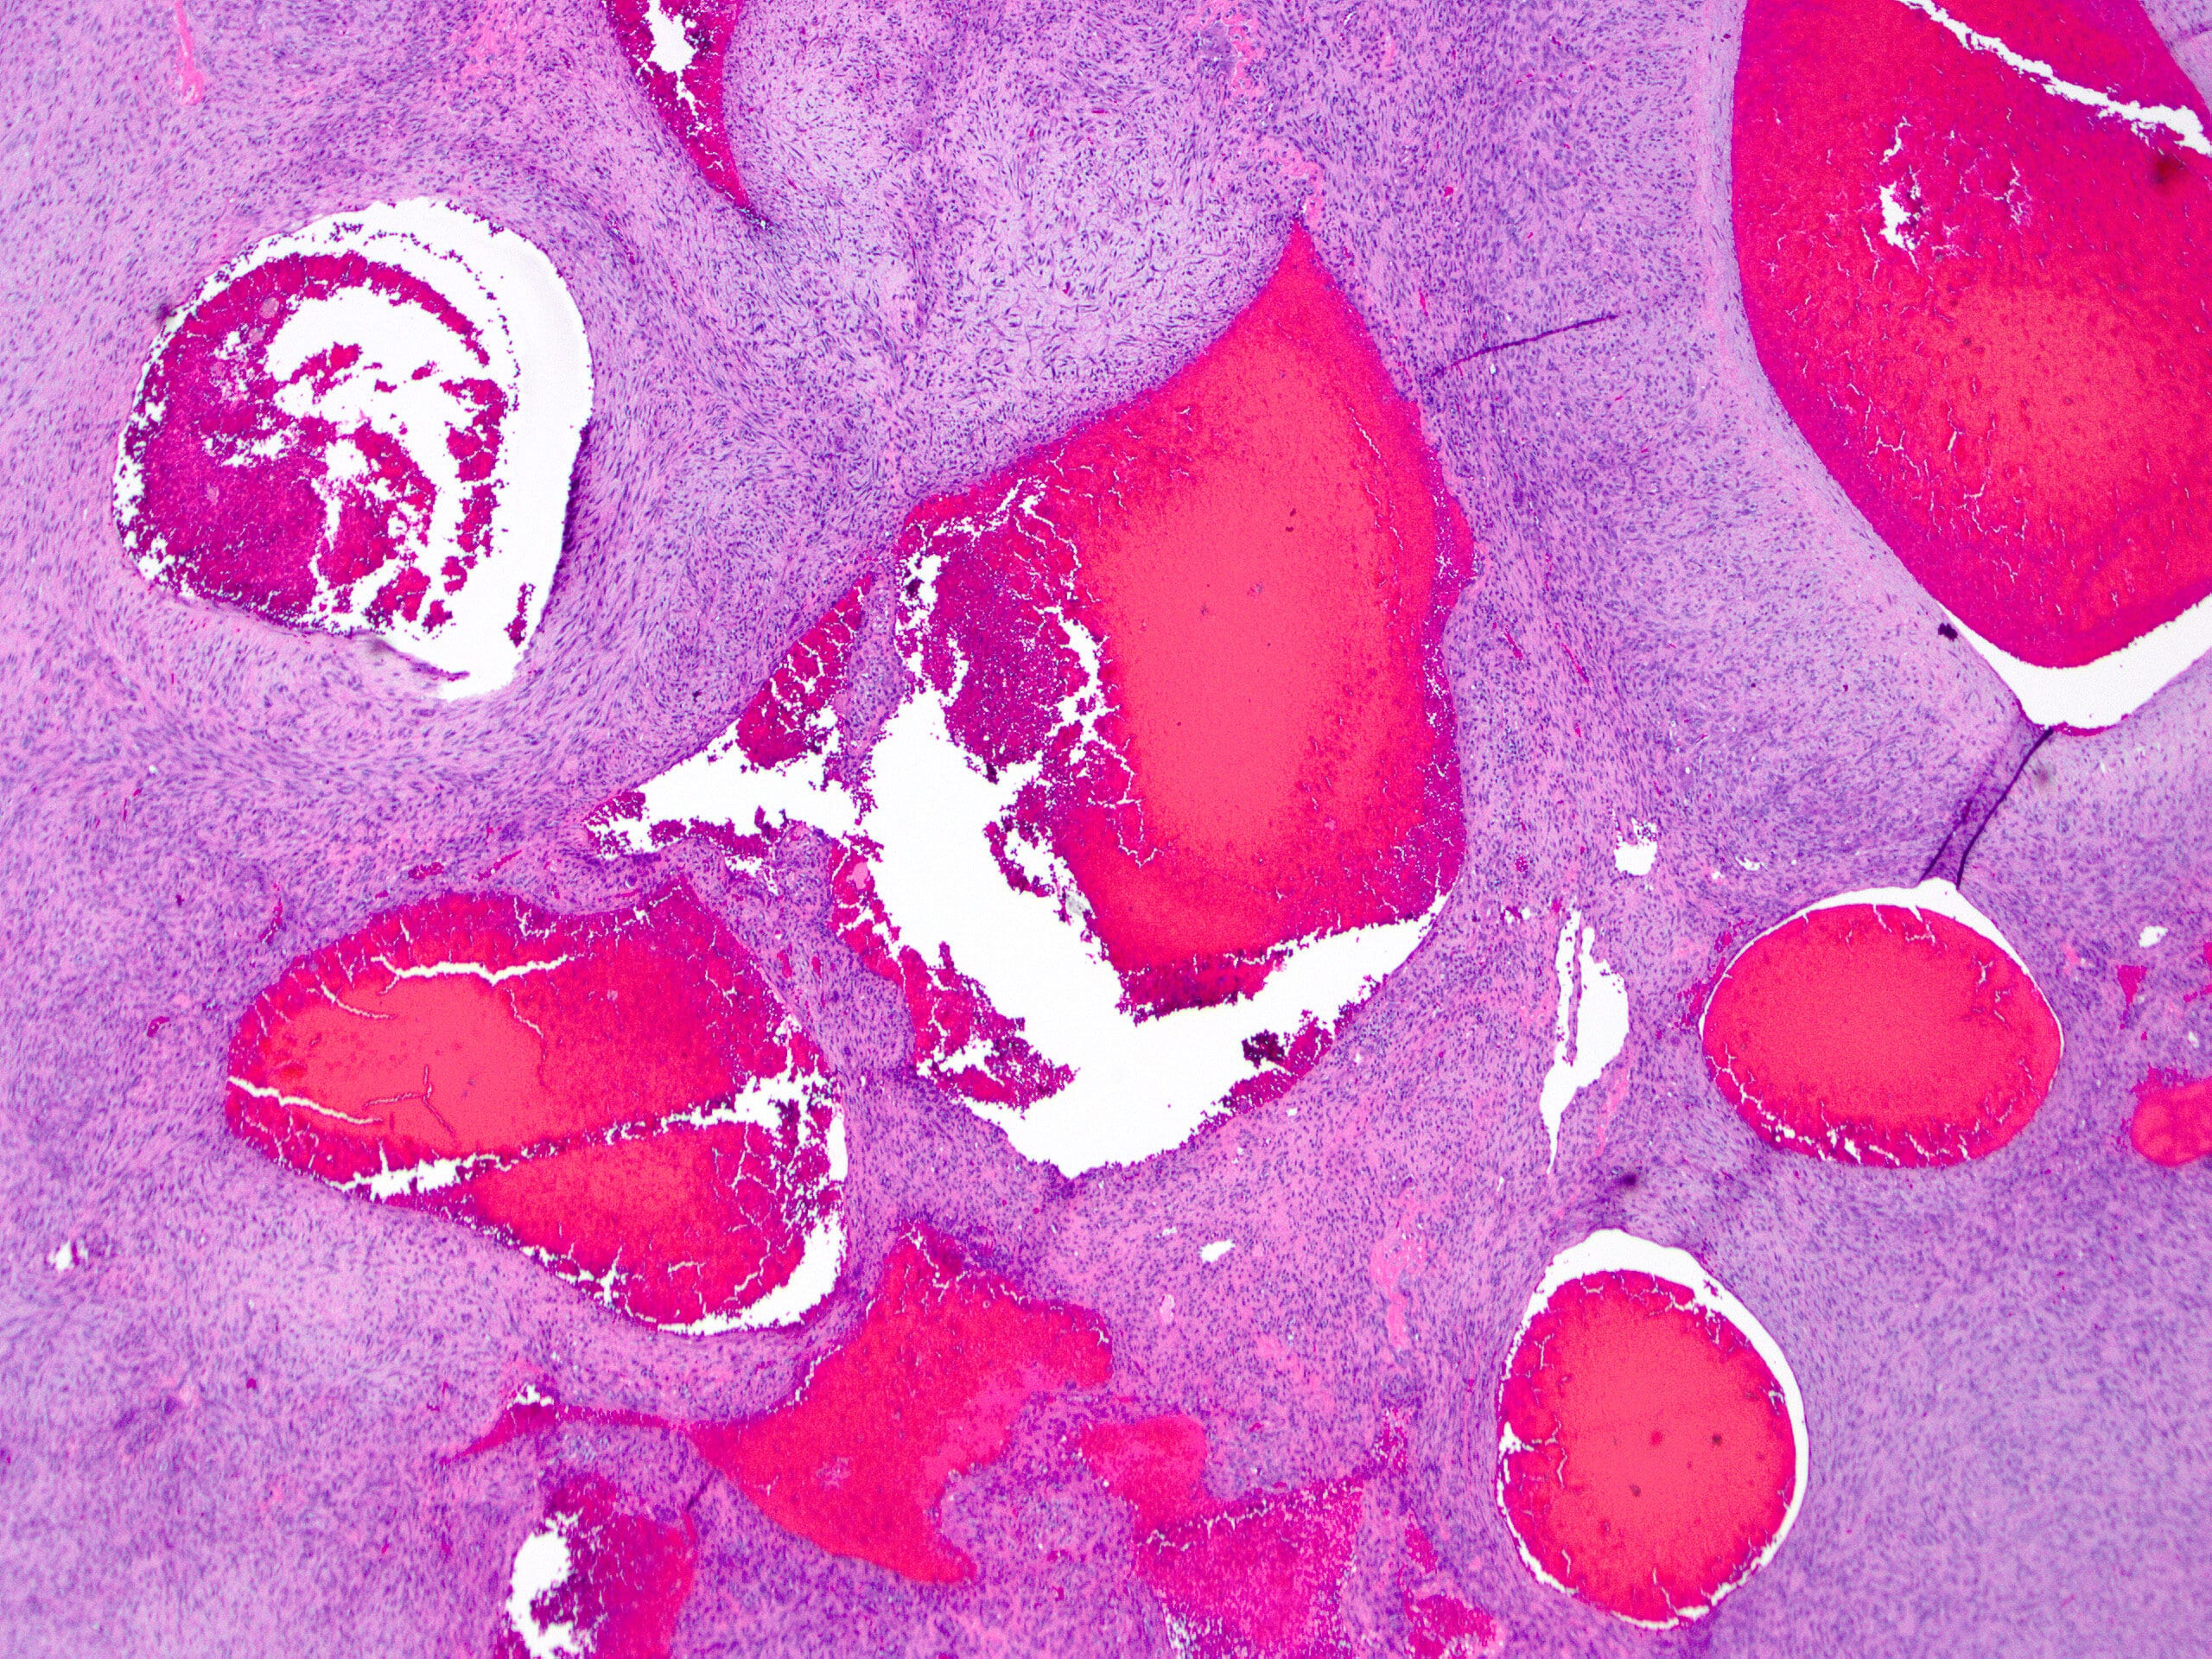

- Spongy, multiloculated, hemorrhagic lesion

- Variable size

- Irregular, sharply demarcated borders with thin shell of reactive bone

- Variable amount of solid component

- Multiloculated cystic lesion

- Blood filled cystic spaces separated by cellular septa containing fibroblasts, giant cells and woven bone

Microscopic (histologic) images

Contributed by Elham Nasri, M.D. and Kelly Magliocca, D.D.S., M.P.H.

A. Aneurysmal bone cyst. The H&E shows cystic spaces with stromal giant cells. Rearrangement of USP6 gene confirms the diagnosis in the above clinical and radiographic context.